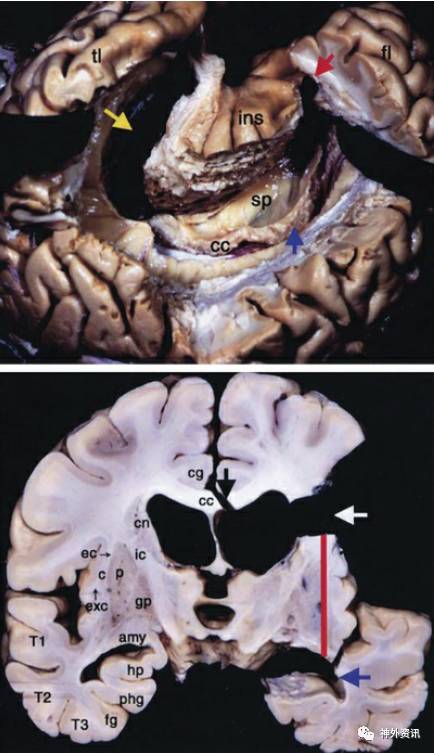

图2. 外侧观呈C形的环岛叶半球离断术(上面照片):侧脑室被彻底打开,黄色箭头指向内侧颞叶被切除的结构,蓝色箭头指向经脑室的胼胝体切开术,红色箭头指向额叶水平的纤维离断术;冠状面环岛的半球离断术(下面照片):白色箭头显示从额叶岛盖部离断内囊纤维的相关区域;黑色箭头显示的经脑室行胼胝体切开术;红线显示内囊切除术;蓝色箭头显示颞干的离断和颞叶内侧结构的离断。C=屏状核,CC=胼胝体,cg=扣带回,cn=尾状核,ec=外囊,fg=梭状回,phg=海马旁回,T1=颞上回,T2=颞中回,T3=颞下回(图片经过Morino允许使用,Anatomical analysis of different hemispherotomy procedures based on dissection of cadaveric brains. J Neurosurg. 2002;97:423-431)